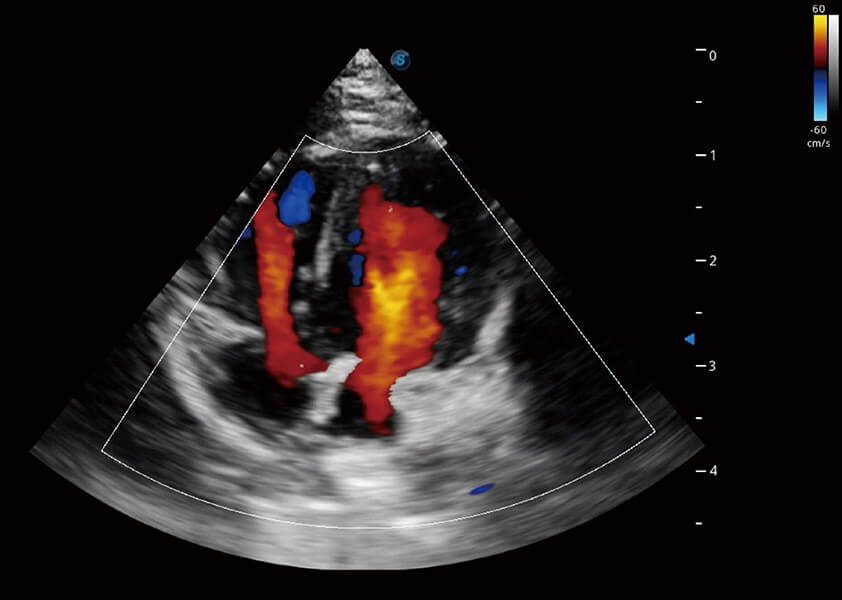

ProPet 60 作為一款高端臺式動物超聲設(shè)備,為動物醫(yī)生的日常診斷提供了一系列貼合動物臨床需求、解決臨床實際問題的高級成像功能。憑借全系列高清探頭,滿足醫(yī)生對腹部、心臟、生殖、淺表、肌骨等成像的所有需求,切實幫助您提升檢查效率,提高診斷信心。

獸用彩色多普勒超聲診斷系統(tǒng)